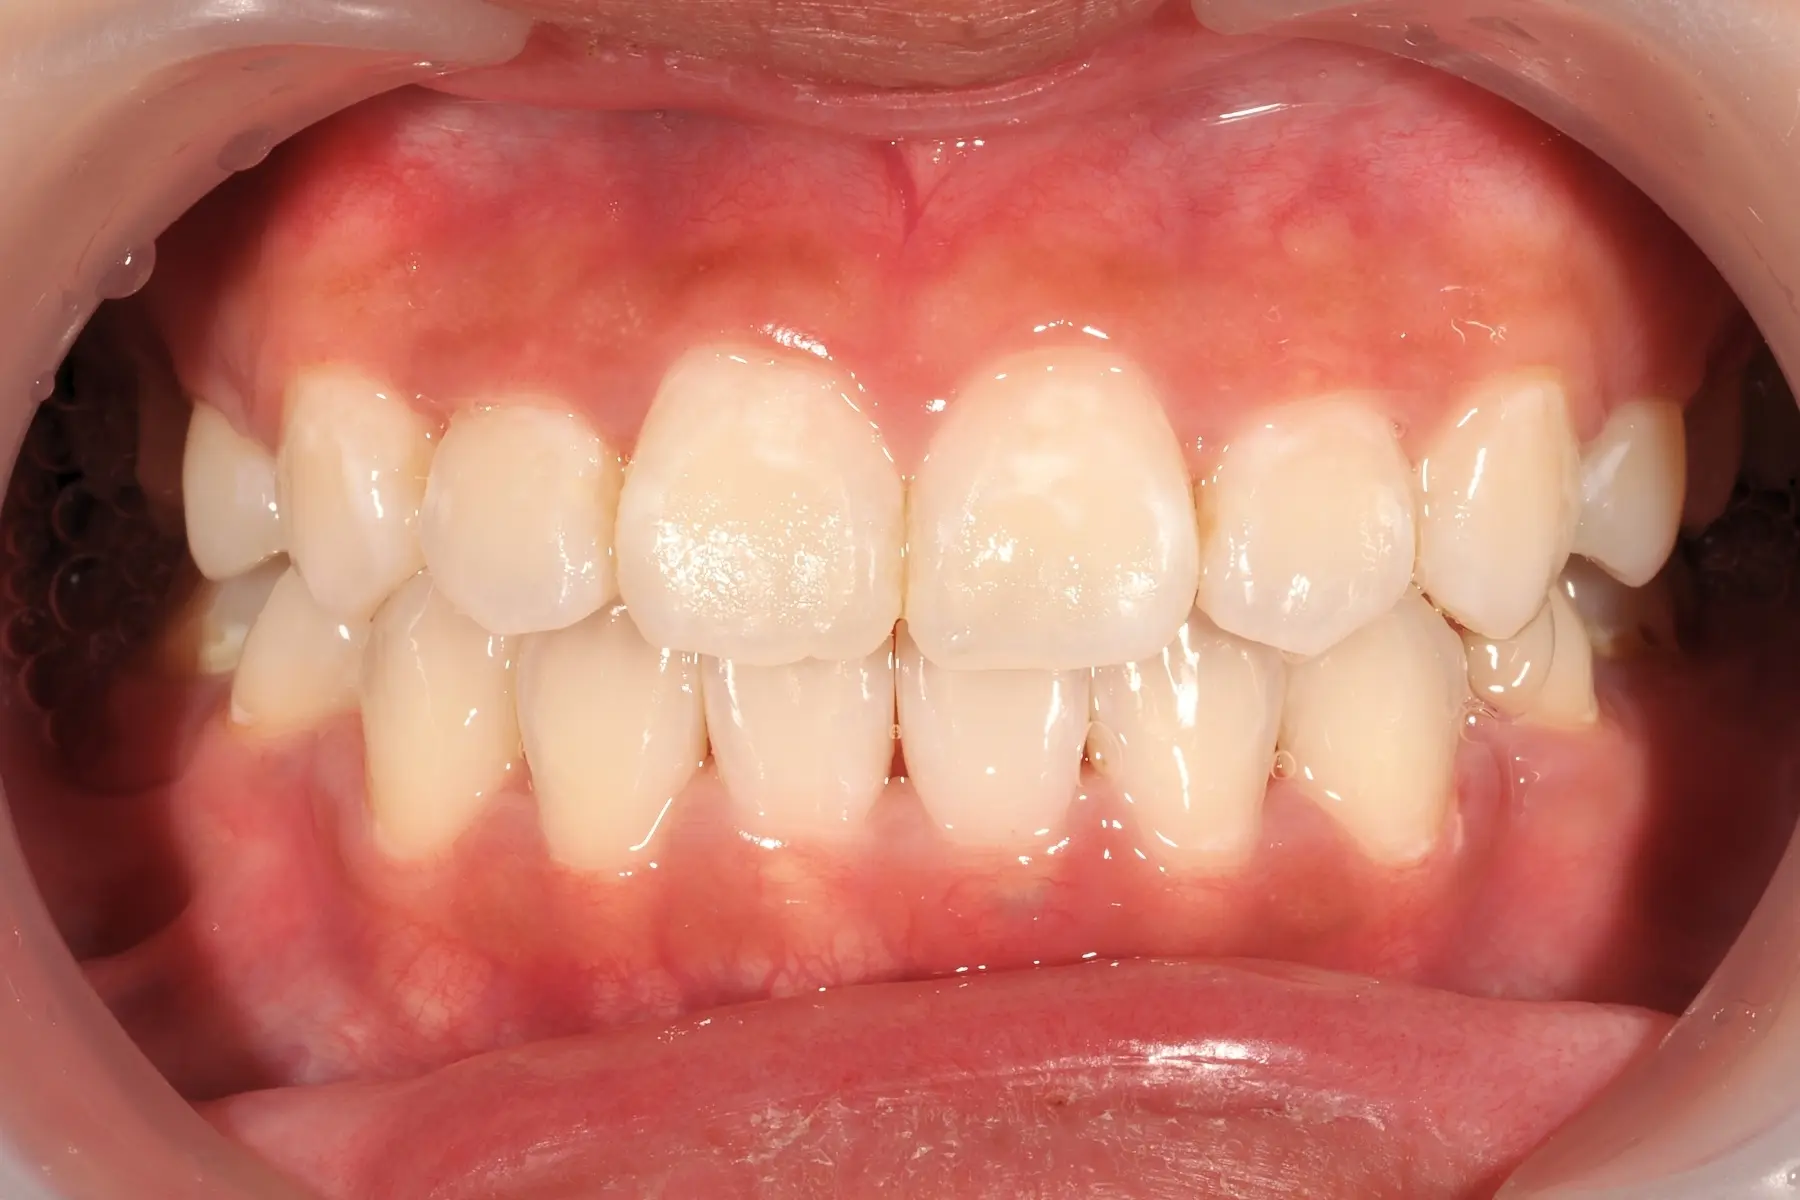

• 術前 43

術後 41

仿生美學樹脂

主治醫師

• 陳暐文

治療時間

單次療程

主訴

矯正完成下排前牙出現黑三角